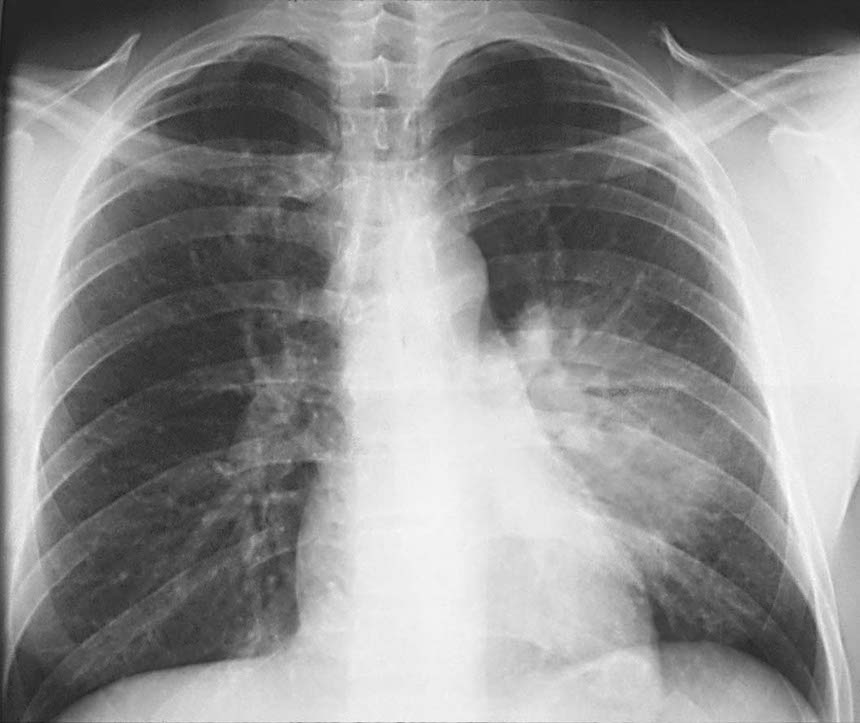

One of the major obstacles in initiating surveillance for HAP is the scarcity of gold-standard diagnostic criteria in non-ventilated patients. Unlike in cases of MRSA or C difficile infection, a surveillance approach on the basis of microbiological diagnosis is unlikely to be effective because high-quality microbiological samples from alveolar regions of the lung are difficult to obtain. Patients at highest risk of HAP tend to be frail. Bronchoscopy is rarely performed in such patients, and sputum samples, the next best non-invasive alternative, might not be feasible (eg, if the patient has a weak cough). However, without criterion-based diagnosis that includes microbiological evidence, overdiagnosis is common.5, 8 Furthermore, in the UK, there is little financial incentive for accurate coding at discharge, making HAP difficult to detect using electronic records alone.